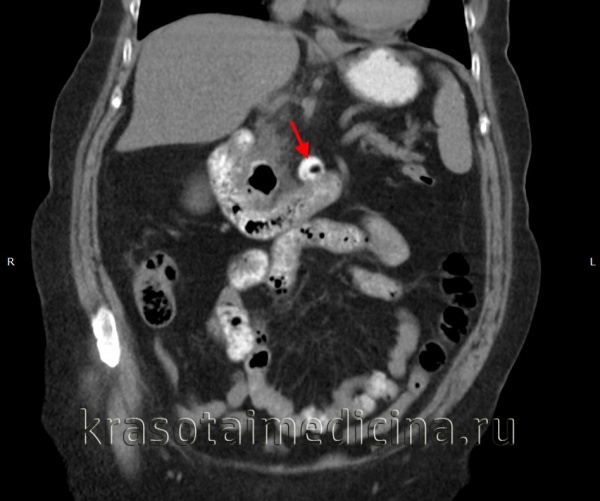

КТ ОБП. Дивертикул горизонтальной части двенадцатиперстной кишки частично заполнен контрастом, частично газом.